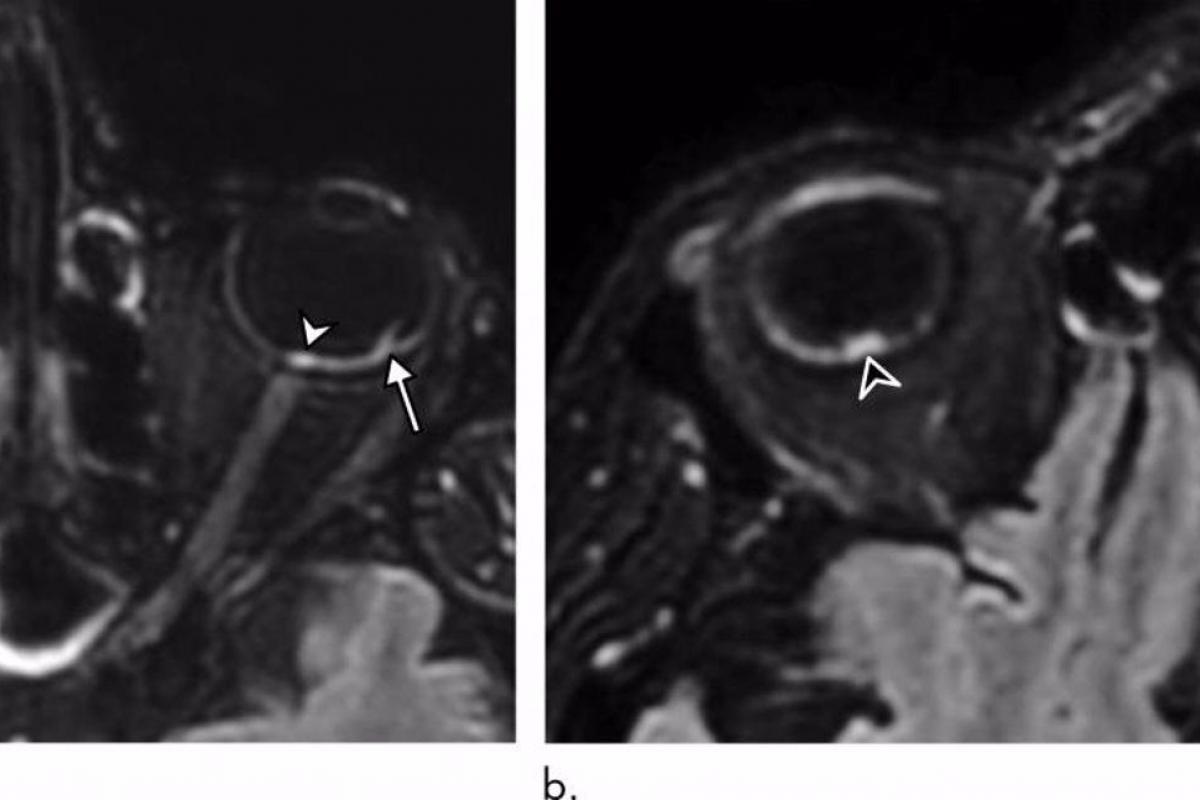

De los 129 pacientes, nueve (7%) tenían hallazgos anormales en la resonancia magnética del globo ocular. Las resonancias magnéticas mostraron uno o más nódulos en la parte posterior, o polo posterior, del globo ocular. Ocho de los nueve pacientes habían pasado un tiempo en la unidad de cuidados intensivos (UCI) por COVID-19.

“Demostramos que algunos pacientes con COVID-19 grave de la cohorte francesa de COVID-19 tenían uno o varios nódulos en el polo posterior del globo ―destaca el autor principal del estudio, Augustin Lecler, profesor asociado de la Universidad de París y neurorradiólogo del Departamento de Neurorradiología del Hospital Fundación Adolphe de Rothschild de París―. Esta es la primera vez que se describen estos hallazgos mediante resonancia magnética”.

Los nueve pacientes tenían nódulos en la región macular, el área en la parte posterior del ojo responsable de nuestra visión central. Ocho tenían nódulos en ambos ojos.

El mecanismo detrás de la formación de nódulos sigue siendo desconocido, dijeron los investigadores, aunque podría estar relacionado con la inflamación provocada por el virus.

El drenaje inadecuado de las venas de los ojos, un problema que se encuentra en los pacientes que pasan tiempo en la UCI en decúbito prono o intubados, también puede ser un factor. Siete de los nueve pacientes con anomalías oculares del estudio habían sido colocados en decúbito prono en la UCI durante un tiempo prolongado.